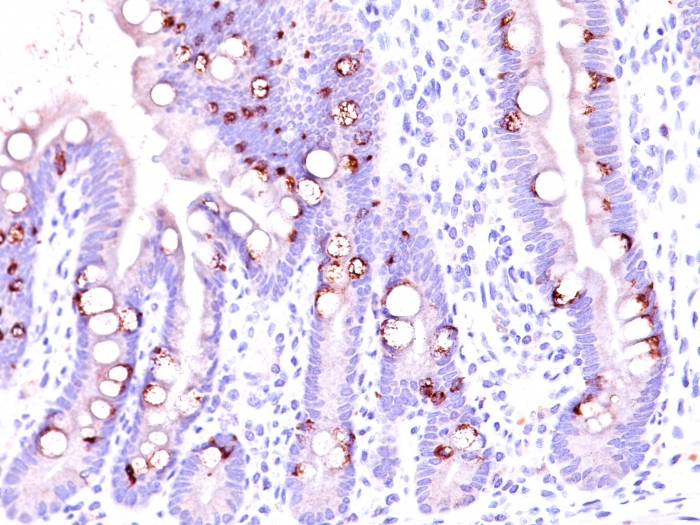

IHC-P analysis of human intestine tissue using GTX34864 MUC2 antibody [CCP58].